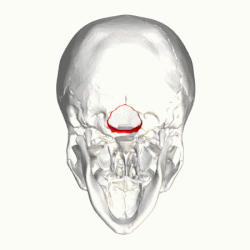

In neurology, the Chiari malformation (/kiˈɑːri/ kee-AR-ee; CM) is a structural defect in the cerebellum, characterized by a downward displacement of one or both cerebellar tonsils through the foramen magnum (the opening at the base of the skull).

By convention, the cerebellar tonsil position is measured relative to the basion-opisthion line, using sagittal T1 MRI images or sagittal CT images.[31] The selected cutoff distance for abnormal tonsil position is somewhat arbitrary, as not every person will be symptomatic at a certain amount of tonsil displacement, and the probability of symptoms and syrinx increases with greater displacement; however, greater than 5 mm is the most frequently cited cutoff number, though some consider 3–5 mm to be "borderline"; pathological signs and syrinx may occur beyond that distance.[31][32][33] One study showed little difference in cerebellar tonsil position between standard recumbent MRI and upright MRI for patients without a history of whiplash injury.[25] Neuroradiological investigation is used to rule out any intracranial condition that could be responsible for tonsillar herniation first. Neuroradiological diagnostics evaluate the severity of crowding of the neural structures within the posterior cranial fossa and their pressure against the foramen magnum. Chiari 1.5 is a term used when both brainstem and tonsillar herniation through the foramen magnum are present.[34]